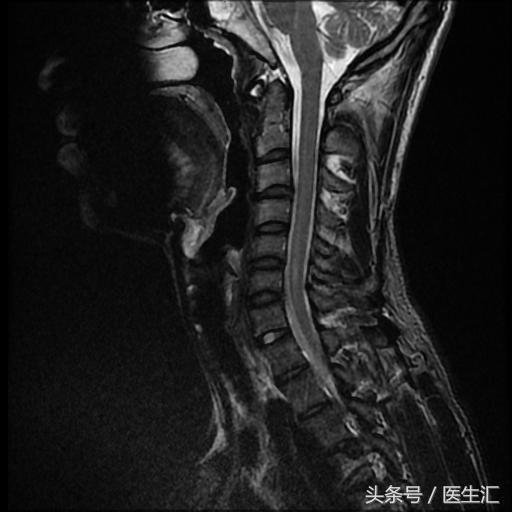

颈MRI:长节段髓内病变(前角)(见图13、14、15、16)

头颅MRI:(见图17)

专家判读:小脑中脚、苍白球、白质、胼胝体皆有病变。